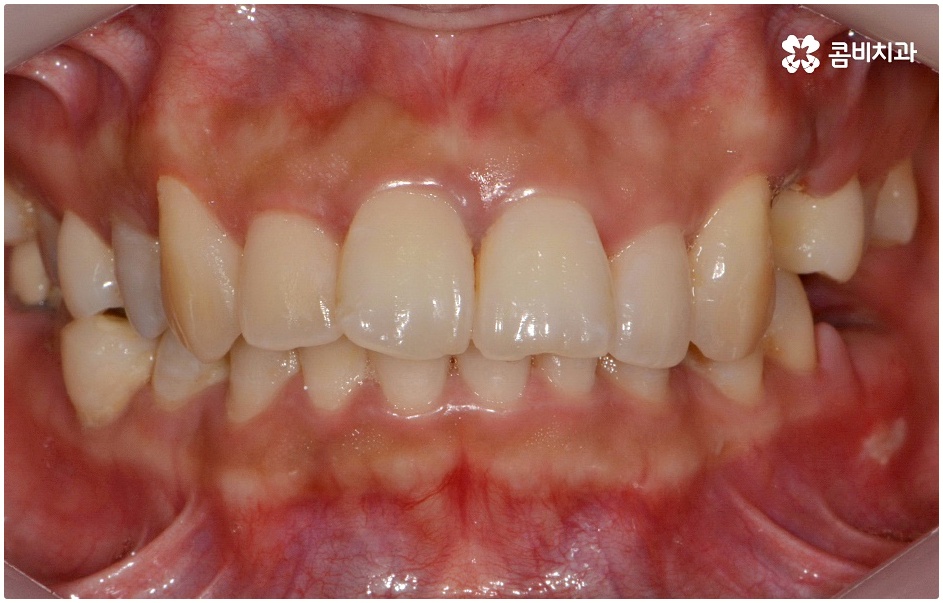

돌출입의 경우 씹기가 불편하고 입을 닫을 때 어려움이 있으며 웃을 때 부자연스러운 입 모양 및 코보다 입이 더 튀어나와 균형이 맞지 않는 옆모습에 대한 심미적인 불만족을 이유로 돌출치아교정 을 고려해 볼 수 있는데요.

돌출입에는 두 가지 경우가 있는데 먼저 치아들의 각도가 앞으로 뻗어서 돌출되는 경우와 골격 구조상 튀어나온 경우 (즉, 치아를 잡아주는 상악 치조골, 잇몸 자체가 돌출된 경우 또는 하악 턱이 뒤로 후퇴한 경우) 이렇게 나눌 수 있으며 정확한 원인을 파악하는 것이 중요하기 때문에 꼼꼼한 검진 및 면밀한 상담이 우선시 될 필요가 있어요.